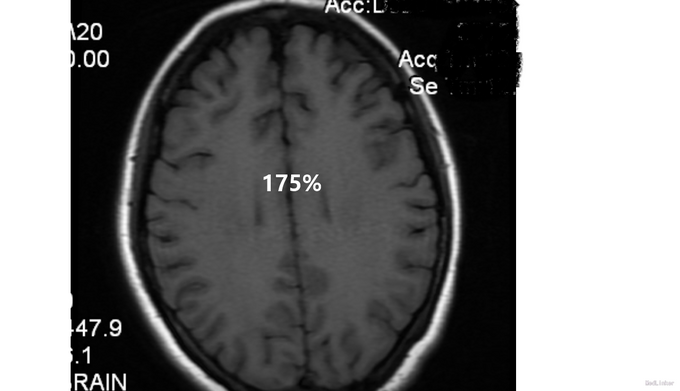

查体:生命体征平稳,心律齐,未闻及病理性杂音,双肺呼吸音清,未闻及干湿罗音。腹软,无压痛及反跳痛,肝脾肋下未及,双下肢不肿。3月21日神经系统检查:意识清楚,回答问题有时不切题,记忆力下降,定向力可,存在幻听,双侧瞳孔等大等圆,光反射灵敏,双侧鼻唇沟对称,伸舌居中,四肢肌力、肌张力、腱反射正常,病理征未引出。颈软,Kernig征阴性,Brudzinski征阴性。3月26日神经系统检查:意识模糊,不能言语,查体不能配合,双侧瞳孔等大等圆,直径约3mm,双侧光反射均迟钝,眼球活动不配合,双侧鼻唇沟尚对称,伸舌不能配合,双上肢肌张力高,四肢肌力查体不配合,可见自主活动,肌力在3级以上。病理征阴性,左侧趾反射弱,疼痛刺激反应减弱,颈强2指,Kernig征双侧阳性,Brudzinski征阴性。 脑脊液检查示:3月26日脑脊液检查:Pro 0.3g/L WBC 48 *10^6抗酸、墨汁染色均为阴性。脑脊液抗NMDA抗体IgG阳性,血抗NMDA抗体IgG 阳性,颅脑MRI平扫+flair+DWI:双侧额颞顶叶皮层下多发异常信号。肿瘤标志物检测(—)。我院子宫肌附件B超提示:右侧卵巢囊肿。